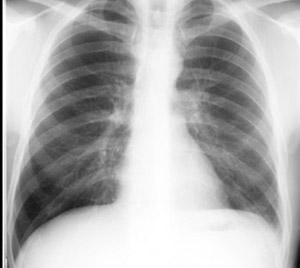

The pleura and pleural spaces are only visible when abnormal. Larger volume aspiration to relieve symptoms of dyspnoea. Ct scans show more detail than. Under normal conditions, pleural fluid is secreted by the parietal pleural capillaries at a rate of 0.01 millilitre per kilogram weight per hour. Can someone clarify what a loculated pleural effusion is?

What are the pulmonary findings? Concave meniscus (horizontal in case of. The pleura and pleural spaces are only visible when abnormal. Obliteration of left costophrenic angle with a wide pleural based dome shaped opacity projecting into the lung noted tracking along the cp angle and lateral chest wall suggestive of loculated pleural effusion, however the possibility of empyema can not be ruled out completely. Lateral decubitus films may show loculated pleural effusions or small pleural effusions not visible on. Larger volume aspiration to relieve symptoms of dyspnoea. Small volume aspiration for diagnosis. Pleura is a mesothelial lined sac that envelopes the lungs and comprises of 2 membranous walls i.e.

Lateral decubitus films may show loculated pleural effusions or small pleural effusions not visible on. Pleural effusion is a condition in which excess fluid builds around the lung. Concave meniscus (horizontal in case of. Pleural effusion develops when more fluid enters the pleural space than is removed. What are the pulmonary findings? Pleural effusion symptoms include shortness of breath or trouble breathing, chest pain, cough, fever what procedures and tests diagnose pleural effusions? Pleural fluid studies were suggestive of a transudative process, though with some abnormal characteristics (including lymphocyte predominance, as well as presence of signet cells). A pleural effusion is accumulation of excessive fluid in the pleural space, the potential space that surrounds each lung.